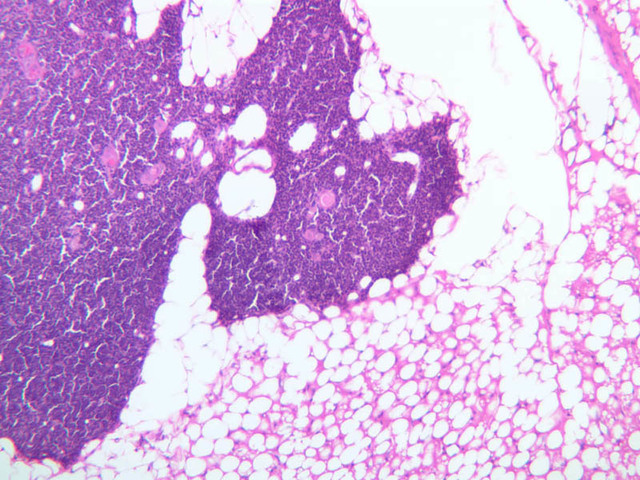

Sections through the spleen (slides A-36, aniline blue [2.5x, 10x, 20x-labeled, 40x] [2.5x, 10x-labeled, 20x-labeled, 40x]; A-37, retic [2.5x, 10x, 20x-labeled, 40x]; A- 37, H&E [2.5x-labeled, 10x, 20x, 40x]; A-38, H&E [10x, 20x, 40x]; A-39, H&E [2.5x, 10x, 20x, 40x]) show a thick investing capsule composed of collagenous tissue and smooth muscle, typically covered with mesothelium. In slide A-36 muscle and collagen are brightly stained. The capsule and mesothelium completely surround the organ and the fibrous portion enters the splenic substance at the hilus around the splenic arteries and veins forming trabeculae of fibromuscular tissue within the splenic substance. This fibromuscular tissue enables the spleen to expel blood by contracting. Identify trabeculae as fibrous partitions in the section and look for blood vessels within them.

Where the trabecular arteries pass into the splenic pulp, they become invested by a sleeve of lymphoid tissue. This lymphatic tissue collectively forms the white pulp of the spleen (A-36 [2.5x, 10x, 20x, 40x]). It also is referred to as the periarterial lymphatic sheath or PALS. On an H&E stained section (A-38 [2.5x, 10x, 20x, 40x] [2.5x, 10x, 20x, 40x]) the white pulp will appear as basophilic clumps of lymphoid cells. The arteries of the white pulp are called central arteries, although they may be displaced to one side of the lymphoid sleeve by the presence of a nodule. The majority of cells forming the PALS are T lymphocytes. In places the covering of lymphatic tissue is enlarged due to the presence of lymphoid nodules (splenic or Malphighian corpuscles) which are comprised predominantly of B lymphocytes.

The remainder of the cellular mass in the spleen is red pulp (A-38 [10x, 20x, 40x]), made up of red and white cells of the blood enmeshed in the reticular tissue of splenic cords and present in the splenic sinuses. After passing through the PALS, the trabecular arteries branch to form smaller arterial vessels known as penicillar arterioles which narrow, forming arterial capillaries that empty into the cords of the red pulp (open circulation) or into the venous sinuses (closed circulation). In the splenic sinuses the cells of the blood are exposed to red pulp macrophages. The splenic sinuses eventually become confluent to form veins that enter the trabeculae and gradually merge meeting in the hilus to form splenic veins.